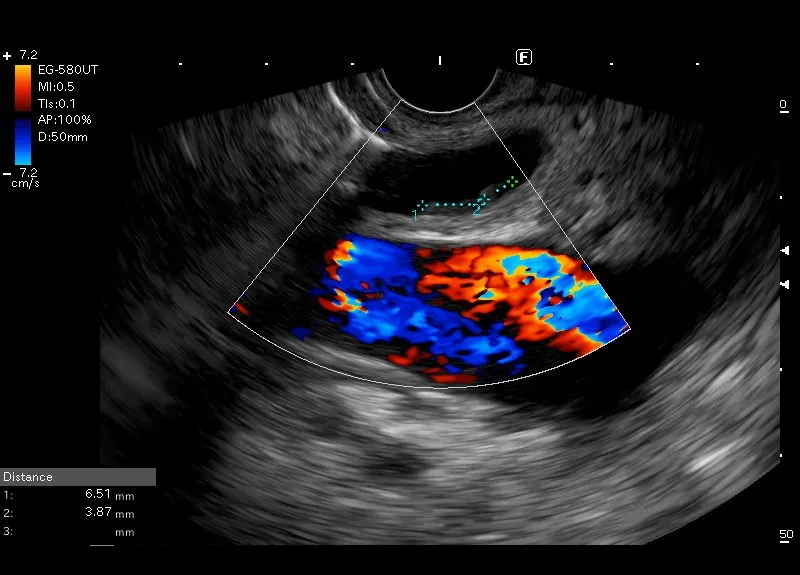

Przyścienne hyperechogeniczne odbicia w poszerzonym przewodzie

żółciowym wspólnym, mogące odpowiadać drobnym „ miękkim „ złogom.